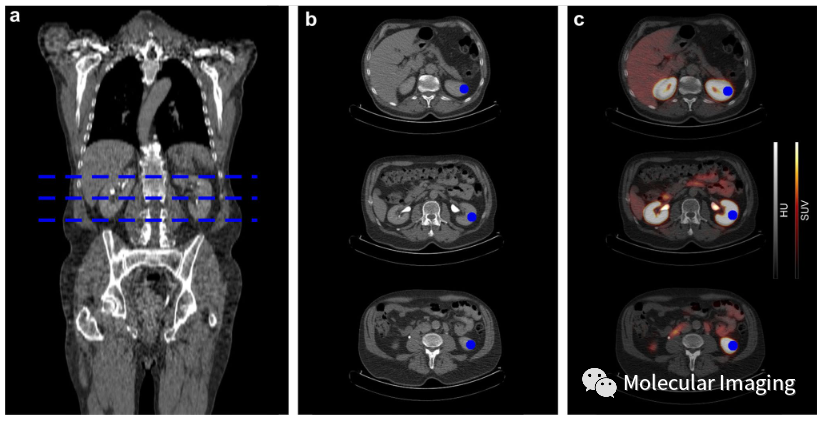

作者的納入標(biāo)準(zhǔn)是2017年8月至2020年10月在亞琛工業(yè)大學(xué)醫(yī)院和海德堡大學(xué)醫(yī)院核醫(yī)學(xué)科使用了上述3種放射性示蹤劑進(jìn)行PET/CT成像的患者。排除標(biāo)準(zhǔn)是無法提供近期影像學(xué)或?qū)嶒炇覚z查數(shù)據(jù)(GFR 和肌酐值異常超過3個月)來確定CKD分期的患者,同時在圖像分析之前接受了腎切除術(shù)或顯示有泌尿系統(tǒng)阻塞跡象的患者也被排除在外。具體的患者情況如表1所示。所有PET/CT圖像的分析由在核醫(yī)學(xué)科擁有多年經(jīng)驗的單個觀察者獨立進(jìn)行,且在確定患者的CKD分期和GFR之前完成。在腎臟的不同位置(上、中、下腎皮質(zhì)),使用SUVmax和SUVmean對三種放射性示蹤劑的腎臟攝取進(jìn)行量化(圖1)。所有研究數(shù)據(jù)使用SPSS 22.0 (SPSS Inc., Chicago, IL) 進(jìn)行統(tǒng)計分析。

圖1 在接受[68Ga]Ga-PSMA PET/CT的患者中測量腎臟示蹤劑攝取的示例